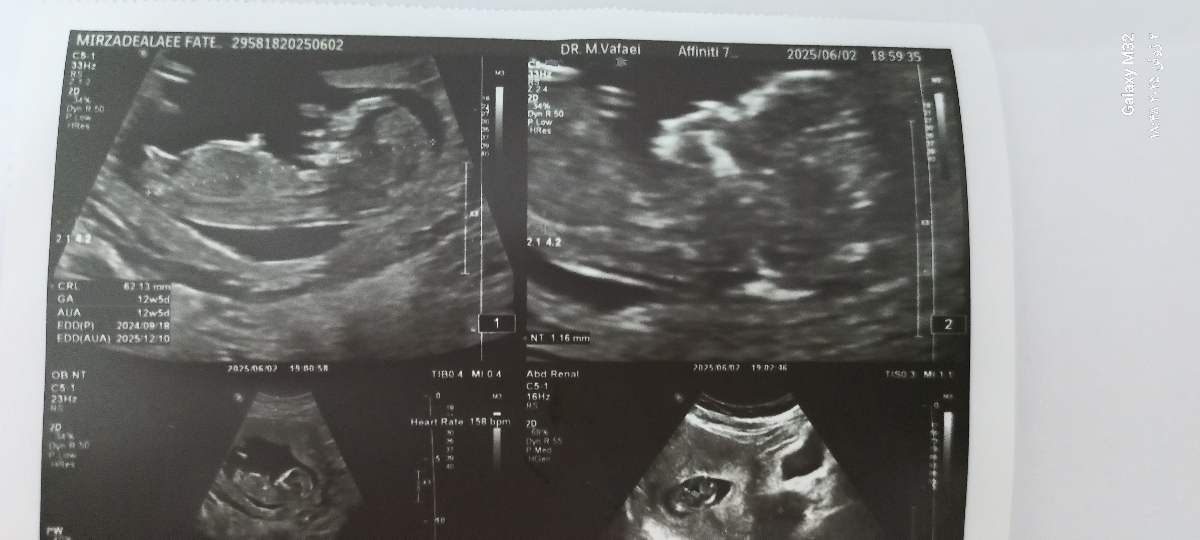

متخصصین ان تی و تعیین جنسیت بیاین حدس بزنین برام

پسره

سلام بنظر پسر

ولی ب دختر میخوره

پسرررر

دختر

بنظر من دختره💜

دختره

به نظر منم دختره.

پسر

رفتم انومالی عزیزم پسر شد